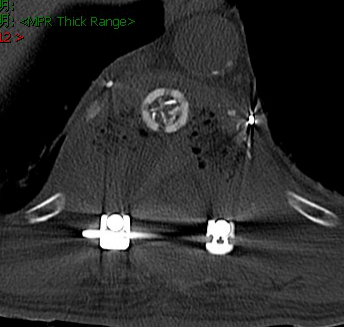

经过慎重考虑,老李决定返乡,并慕名来到我院就诊。脊柱外三科主任陈海龙看到老李的脊柱DR片后,顿感情况不妙,胸11椎体高度降低,椎体骨质及右侧附件结构严重破坏,幸运的是老李目前没有神经损伤症状,否则严重的话可造成双下肢截瘫。陈主任安排医师为老李紧急办理了住院手续,一边叮嘱他绝对卧床,一边加快各项相关检查。结合他的CT及MRI等影像资料显示,结果不过容乐观,不出所料,胸11肿瘤毫无疑问,而后穿刺活检的病理结果再次证实了医生的判断:骨巨细胞瘤。但幸运的是,经过全面彻底排查,未见肿瘤转移,那么此时此刻对老李来讲,完整彻底地切除肿瘤,是最优的选择。

脊柱整块切除术(En-block技术)能完整切除肿瘤组织,最大限度减少肿瘤细胞的扩散,降低肿瘤的复发。但此术式)属于高难度,高风险手术,难点有二:第一,术中出血,肿瘤组织血供异常丰富,术中大量失血可造成失血性休克甚至死亡。第二,肿瘤组织临近脊髓,术中操作稍有不慎,都有可能损伤脊髓导致下肢瘫痪甚至截瘫。

在困难面前,我院脊柱外三科团队没有退缩,在精心策划手术方案后,首先请介入科为老李做了节段血管栓塞,以减少术中出血,而后由陈海龙主任医师主刀,带领主治医师马俊杰、管床医师朱博组成的手术团队,在麻醉医师紧密配合下与全程神经监测保护下,细致分离神经血管,小心保护脊髓组织,成功完整地切除了病变椎体及附件,并应用人工椎体及脊柱钉棒系统重新建立脊柱稳定性,以便老李早期下地活动。在脊柱外三科团队的共同努力下,手术历经四个多小时,取得圆满成功,术中没有任何神经损伤症状出现,术后一周患者老李已经在支具保护下下床活动。